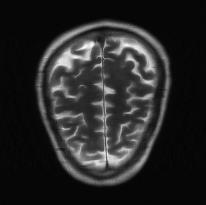

Recently, deep neural networks have greatly advanced undersampled Magnetic Resonance Image (MRI) reconstruction, wherein most studies follow the one-anatomy-one-network fashion, i.e., each expert network is trained and evaluated for a specific anatomy. Apart from inefficiency in training multiple independent models, such convention ignores the shared de-aliasing knowledge across various anatomies which can benefit each other. To explore the shared knowledge, one naive way is to combine all the data from various anatomies to train an all-round network. Unfortunately, despite the existence of the shared de-aliasing knowledge, we reveal that the exclusive knowledge across different anatomies can deteriorate specific reconstruction targets, yielding overall performance degradation. Observing this, in this study, we present a novel deep MRI reconstruction framework with both anatomy-shared and anatomy-specific parameterized learners, aiming to "seek common ground while reserving differences" across different anatomies.Particularly, the primary anatomy-shared learners are exposed to different anatomies to model flourishing shared knowledge, while the efficient anatomy-specific learners are trained with their target anatomy for exclusive knowledge. Four different implementations of anatomy-specific learners are presented and explored on the top of our framework in two MRI reconstruction networks. Comprehensive experiments on brain, knee and cardiac MRI datasets demonstrate that three of these learners are able to enhance reconstruction performance via multiple anatomy collaborative learning.